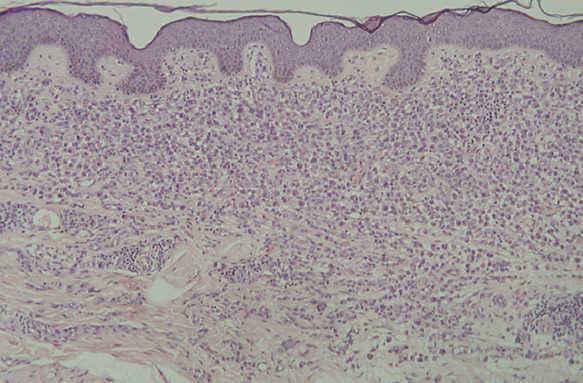

En la HCL el infiltrado se localiza normalmente en la dermis adventicial, y puede invadir la epidermis, produciendo clínicamente lesiones erosivas (figs. 13 y 14). En las formas nodulares puede invadir la hipodermis. En pacientes adultos se ha descrito la distribución del infiltrado alrededor de los anejos (figs. 15 y 16) 13. Aparecen otras células inflamatorias en número variable, sobre todo neutrófilos, eosinófilos, linfocitos y mastocitos y, en menor medida, células gigantes multinucleadas. De forma clásica se han descrito tres subtipos principales: proliferativo, granulomatoso y xantomatoso, que se intentan correlacionar con las diferentes formas clínicas. Histológicamente no existen diferencias entre la HCL y la reticulohistiocitosis congénita autoinvolutiva 7.

Fig. 15.--Infiltrado de células de Langerhans rodeando los folículos pilosos. (Hematoxilina-eosina, x10.)

Fig. 16.--Detalle del infiltrado rodeando los anejos. (Hematoxilina-eosina, x20.)